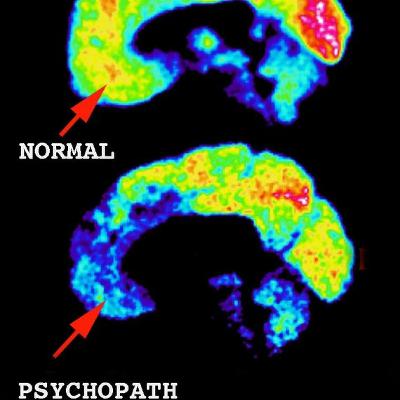

A neuroscientist makes an unsettling discovery.